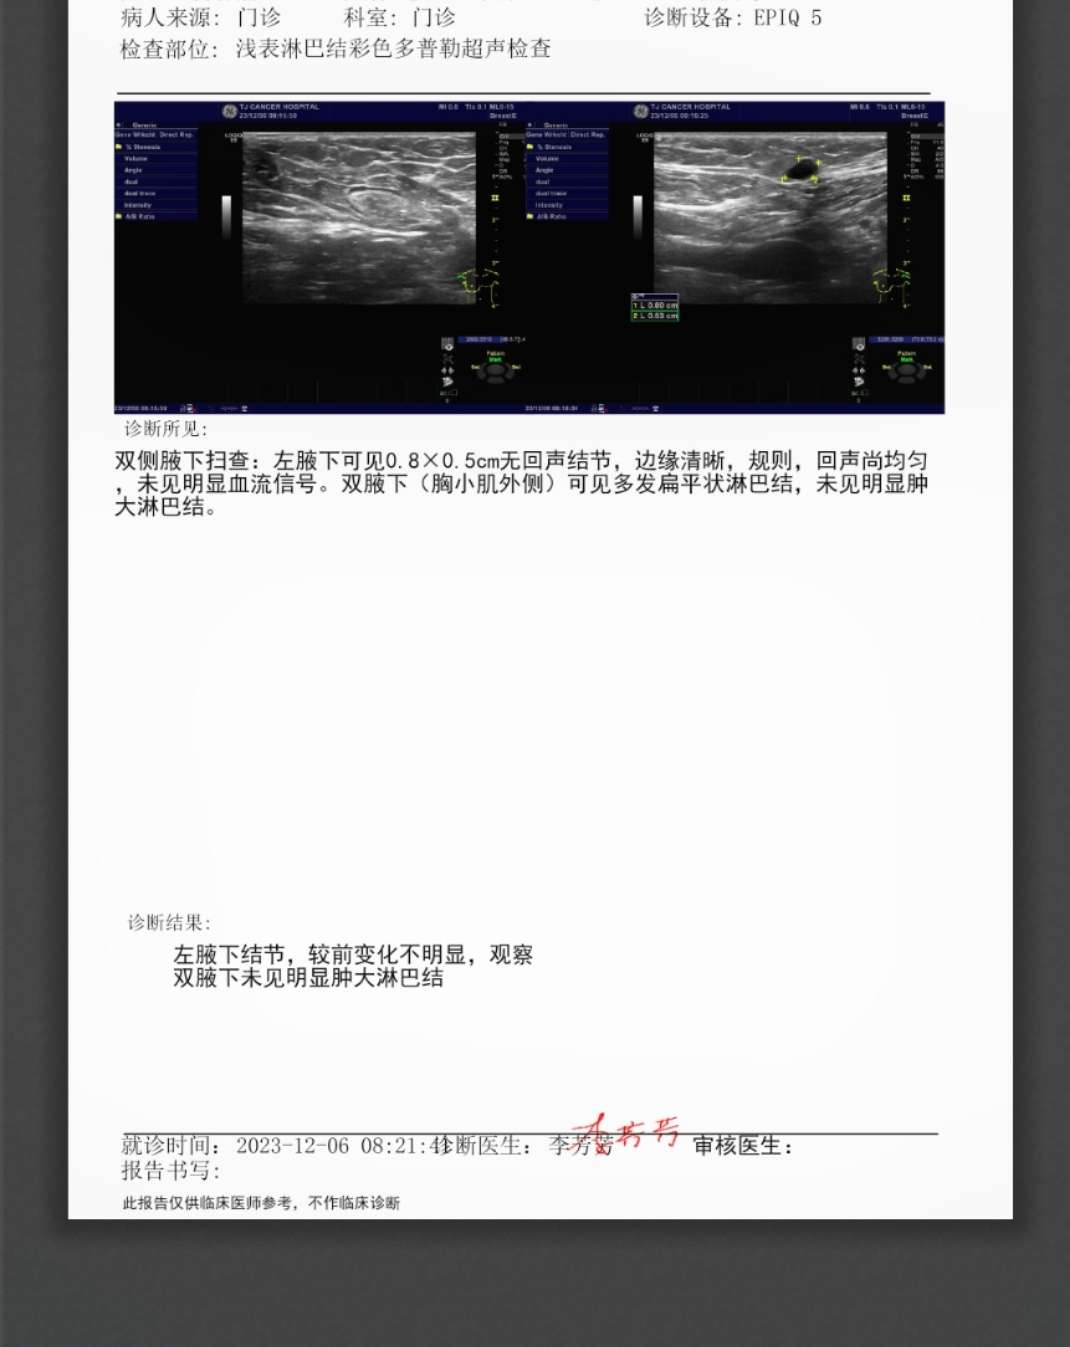

这张是去年12月份的

2024-05-27 12:15:15 有用(0)